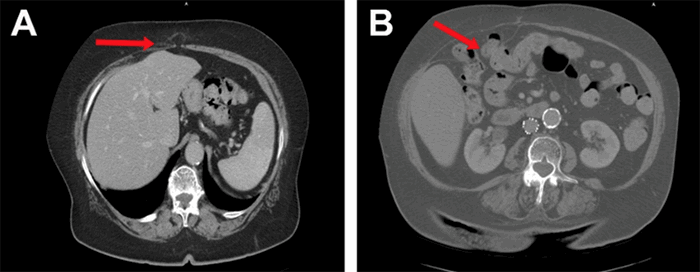

Figure 1. Subcentimeter Fascial Defects Seen in the Midline Epigastrium. Published with Permission

A) Midline upper epigastric 8 mm fascial defect; B) Right upper-quadrant posterior rectus sheath hernia containing colon, along with attenuated/atrophic overlying right rectus abdominis muscle

An 89-year-old female with a past surgical history of an open cholecystectomy via Kocher incision among other abdominal surgeries presented to the surgical clinic complaining of intermittent daily "pins and needles" abdominal pain in the left lower quadrant (LLQ) with radiation to the left upper quadrant (LUQ), not associated with any particular trigger. She also complained of an extensive history of constipation, managed with milk of magnesia. A CT of the abdomen and pelvis demonstrated a large fascial defect of the posterior rectus sheath in the right upper quadrant (RUQ), without disruption of the overlying right rectus muscle or the anterior rectus sheath. The hernia contained a nonobstructed loop of colon. In addition, two subcentimeter fascial defects were seen in the midline epigastrium (Figure 1). The patient was noted to have a RUQ bulge adjacent to her previous Kocher incision on physical exam. Diagnosis was made of a 6.2 cm × 5 cm bowel-containing RUQ posterior rectus sheath hernia with intact rectus muscle. After medical optimization, the patient was scheduled for a laparoscopic incisional hernia repair with mesh.